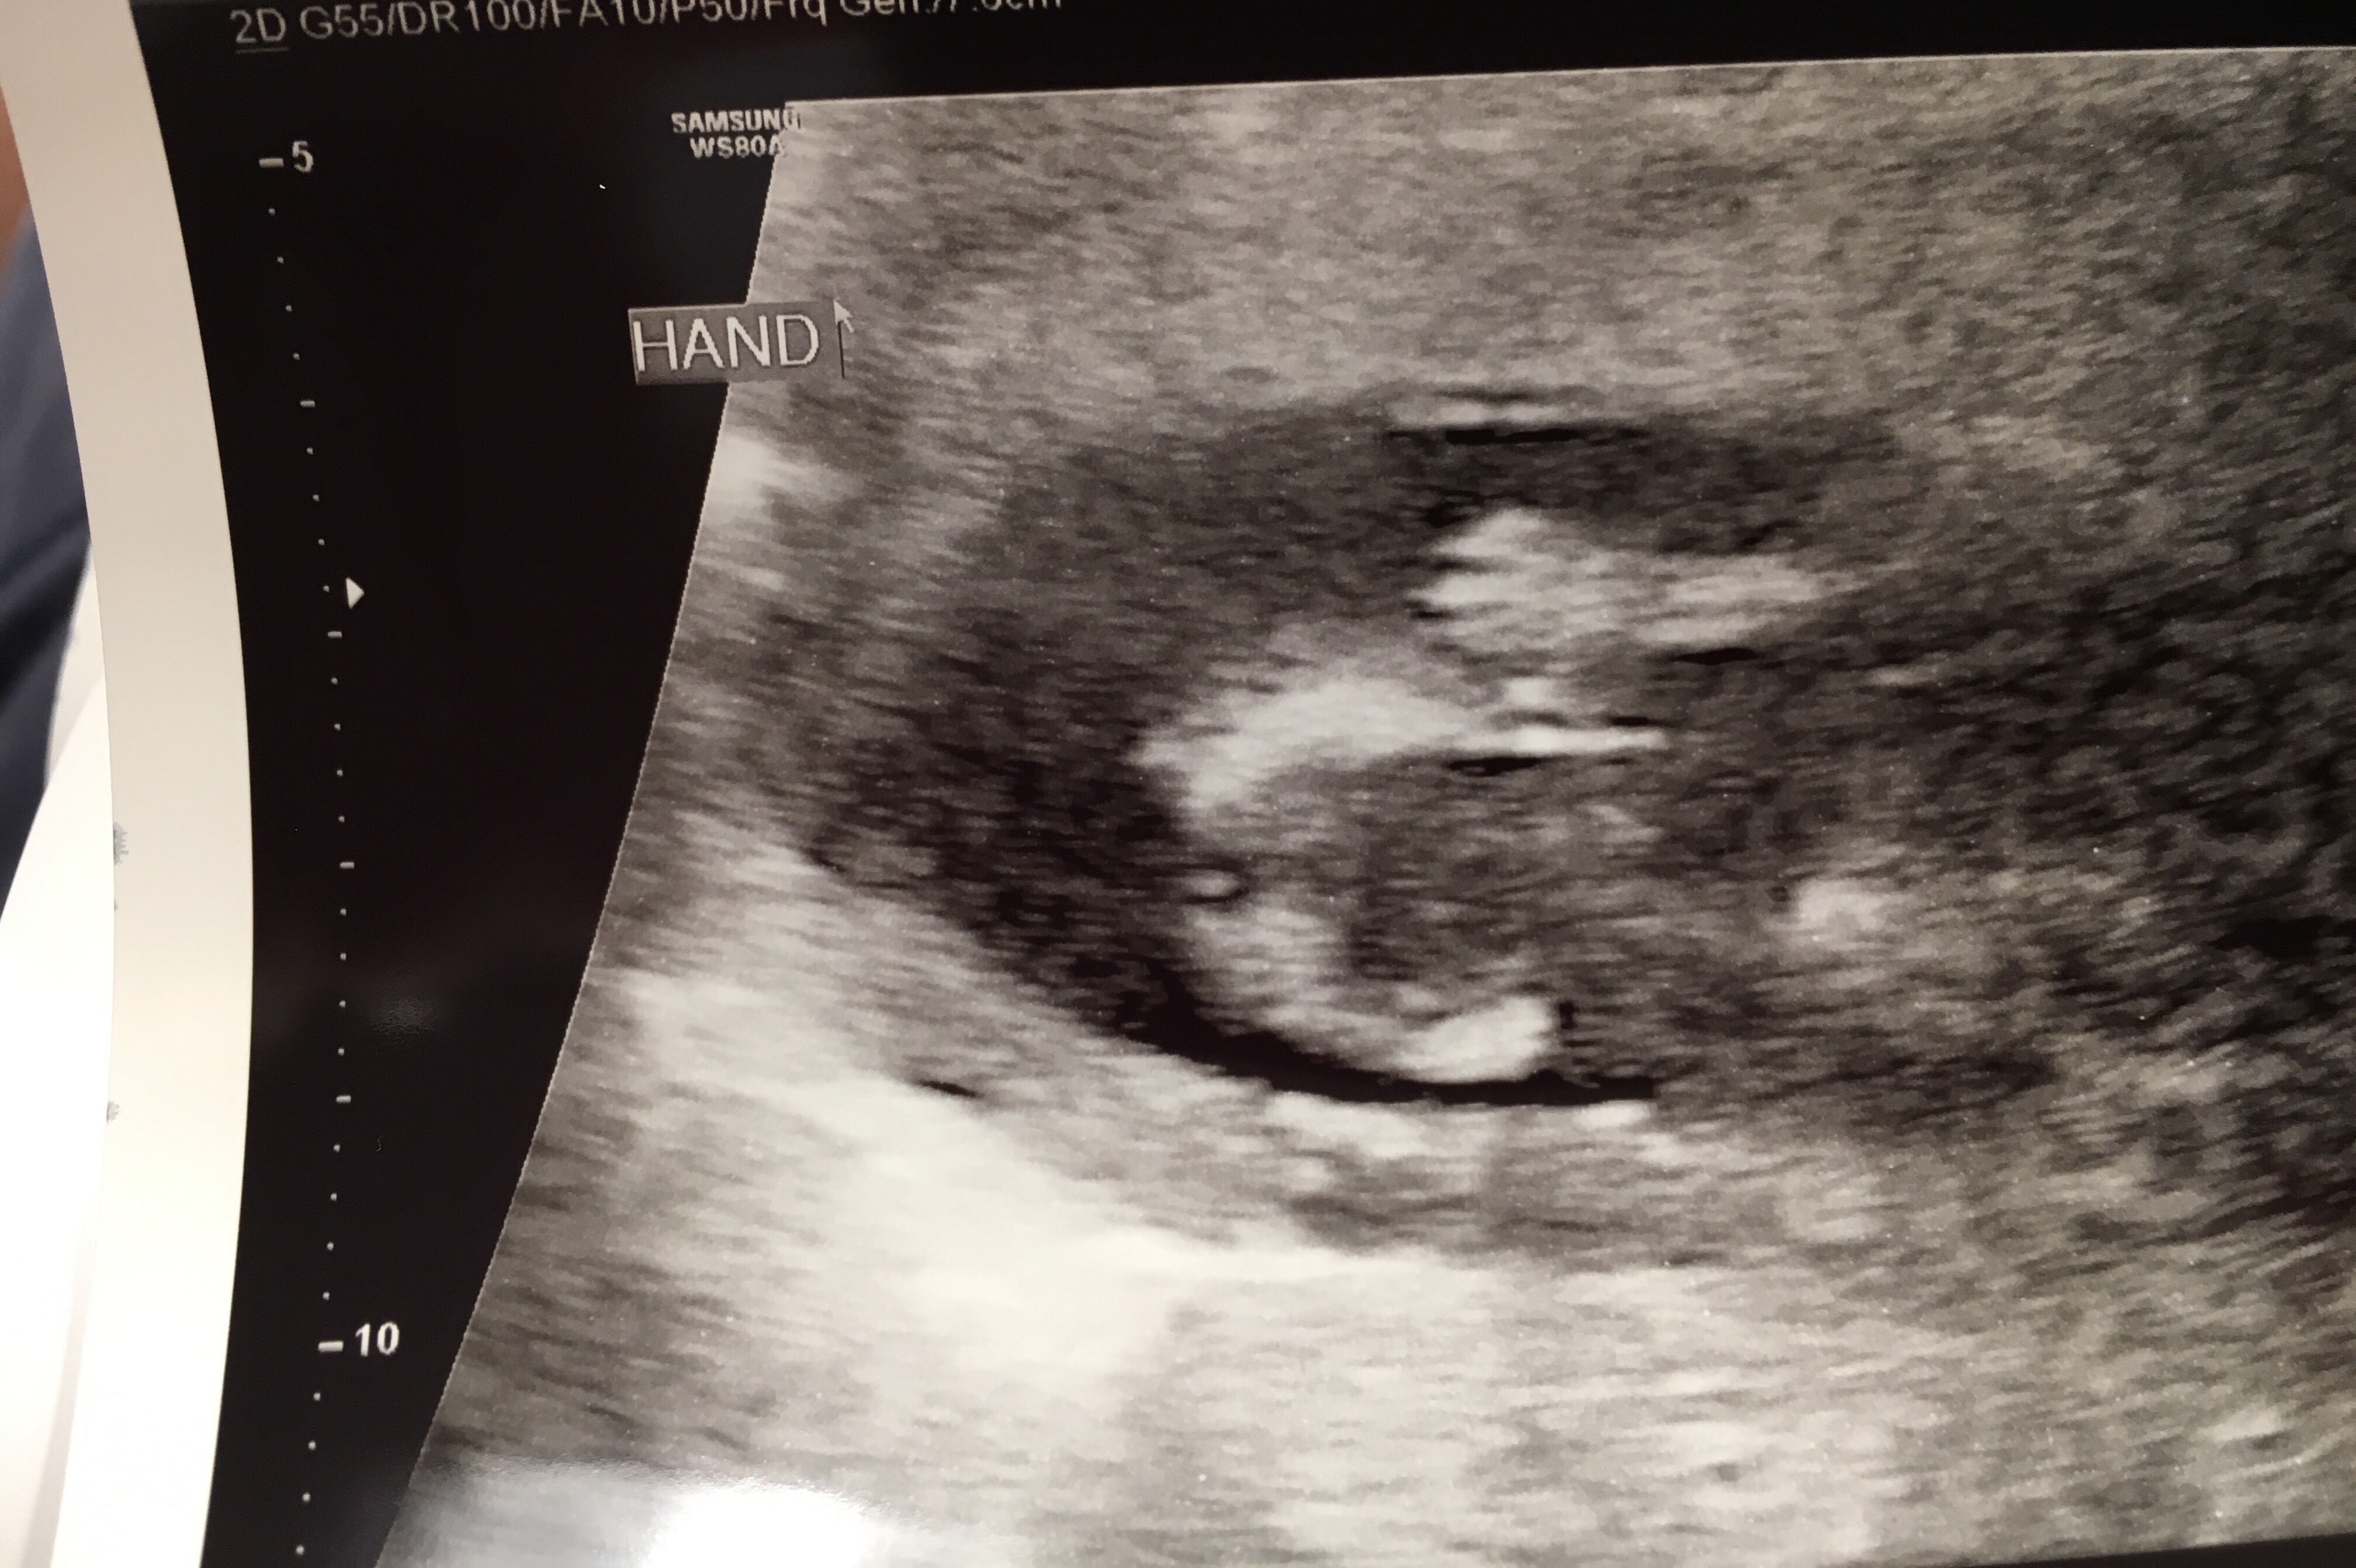

Our NT scan went well! They want the measurement to be below 3, and little miss was 1.3.

She kept dancing the whole scan. She never stopped. I’m actually already feeling her movements, and now I know why!

And, as promised…

Profile view 🙂

all the little fingers

laying with her hand above her head